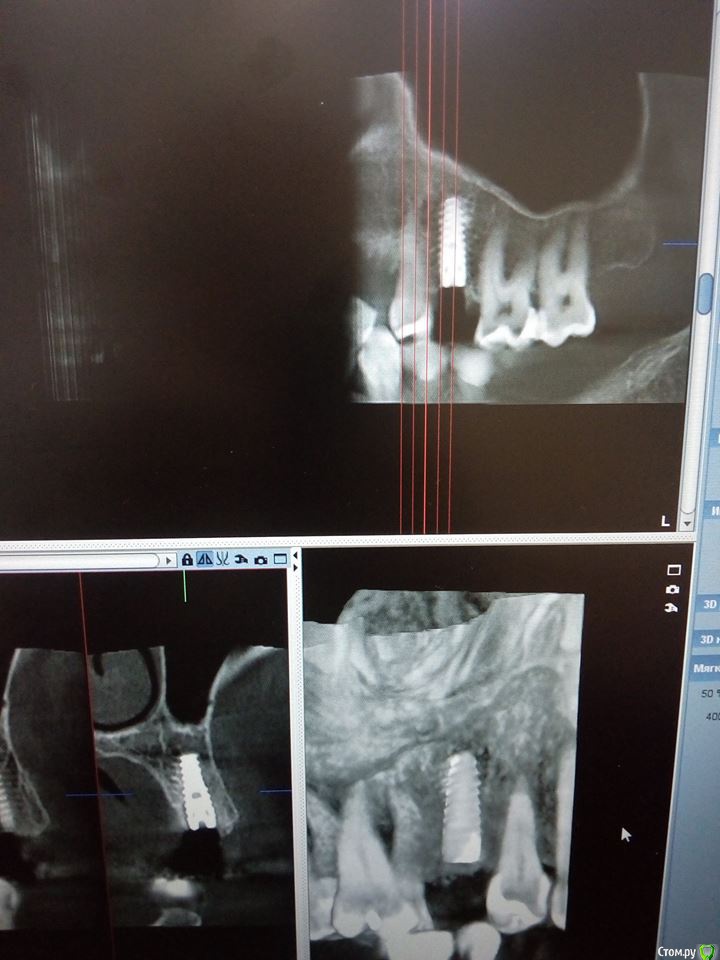

Sampson Опубликовано 10 августа, 2018 Поделиться Опубликовано 10 августа, 2018 (изменено) Очень мило для первого раза.. Здравствуйте коллеги.Сегодня поставил первый свой одномоментныйИзначальная картинаУдалениеСверление и контрольГрафтБолтКТФдмP.S. еще сдт взял с неба и вестибулярно подшил. А с неба заложил prf. Изменено 10 августа, 2018 пользователем Sampson 7 Ссылка на комментарий

Sampson Опубликовано 13 августа, 2018 Автор Поделиться Опубликовано 13 августа, 2018 Через 2 суток Ссылка на комментарий